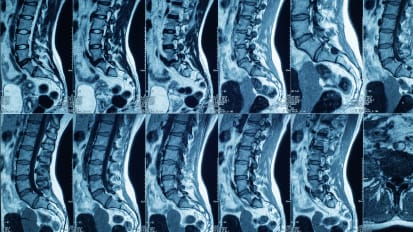

Leading-Edge Approaches and Research to Improve Surgical Spine Treatments and Outcomes

Spine neurosurgeons use technologies co-developed by faculty members to advance patient care. Plus, a first-of-its-kind lab creates a new class of implantable, wearable medical devices to aid those with spinal cord injuries.